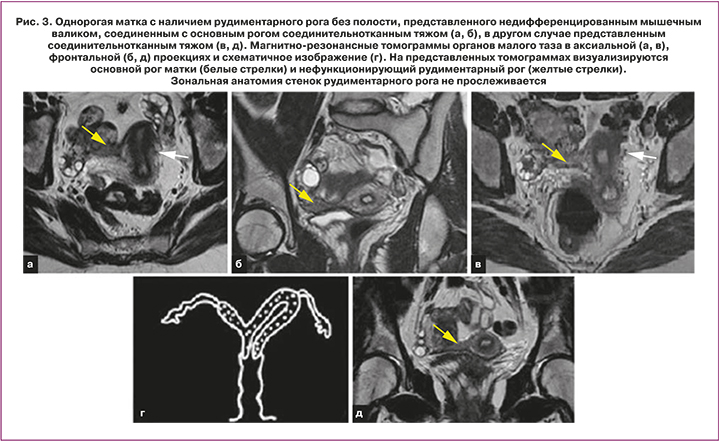

Ключевые признаки: типичный сформированный рудиментарный рог визуализируется, как изогнутая мягкотканная структура малых размеров, локализованная латерально от срединной линии с нормальной зональной анатомией стенок (функциональный эндометрий, переходно-соединительная зона, миометрий). Рудиментарный рог без полости выглядит, как однородное низкой или средней интенсивности МР-сигнала мягкотканное образование (рис. 3). При наличии замкнутого (не сообщающегося) рудиментарного рога с функционирующим эндометрием у взрослых женщин визуализируется гематометра. Кроме того, могут быть выявлены признаки эндометриоза [10].

Основной рог принимает изогнутую и удлиненную, «бананообразную» форму. При этом объем матки уменьшается, ее конфигурация становится асимметричной. Нормальная зональная анатомия присутствует, но эндометрий может быть атипично тонким, сужающимся к вершине рога (форма «пули») [5].